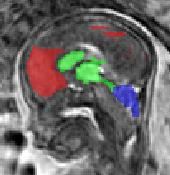

Limiting failures of machine learning systems is of paramount importance for safety-critical applications. In order to improve the robustness of machine learning systems, Distributionally Robust Optimization (DRO) has been proposed as a generalization of Empirical Risk Minimization (ERM). However, its use in deep learning has been severely restricted due to the relative inefficiency of the optimizers available for DRO in comparison to the wide-spread variants of Stochastic Gradient Descent (SGD) optimizers for ERM. We propose SGD with hardness weighted sampling, a principled and efficient optimization method for DRO in machine learning that is particularly suited in the context of deep learning. Similar to a hard example mining strategy in practice, the proposed algorithm is straightforward to implement and computationally as efficient as SGD-based optimizers used for deep learning, requiring minimal overhead computation. In contrast to typical ad hoc hard mining approaches, we prove the convergence of our DRO algorithm for over-parameterized deep learning networks with ReLU activation and a finite number of layers and parameters. Our experiments on fetal brain 3D MRI segmentation and brain tumor segmentation in MRI demonstrate the feasibility and the usefulness of our approach. Using our hardness weighted sampling for training a state-of-the-art deep learning pipeline leads to improved robustness to anatomical variabilities in automatic fetal brain 3D MRI segmentation using deep learning and to improved robustness to the image protocol variations in brain tumor segmentation. Our code is available at https://github.com/LucasFidon/HardnessWeightedSampler.